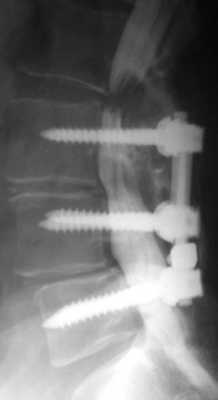

Применение жестких фиксирующих систем при спондилодезах «выключают» один или несколько позвоночно-двигательных сегментов из кинематической цепи позвоночного столба. Смежные сегменты испытывают значительную механическую перегрузку, что приводит к преждевременной деградации дисков и суставов смежного уровня, разрастанию соединительной ткани, компенсаторной гипертрофии дугоотростчатых суставов, приводящих к развитию сегментарного стеноза. Рецидивная грыжа диска и неустраненный стеноз позвоночного канала требуют повторного хирургического вмешательства.

Синдром смежного уровня. Стеноз позвоночного канала выше уровня стабилизации. Миелография.

МРТ поясничного отдела позвоночника. Синдром смежного уровня. Нестабильность позвоночного сегмента выше уровня стабилизации.